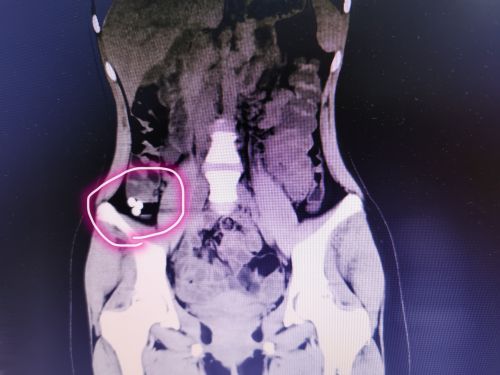

腹部X光检查发现,小可的右下腹有3枚圆形异物,张先华主任医师和龙毅副主任医师仔细为小可进行体查,耐心询问病史,结合CT结果,确诊为肠道异物。由于异物系3枚纽扣电池,一次性取出十分困难,发生肠梗阻、肠粘膜损害导致肠穿孔的风险大;考虑到电池已经进入结肠,自行排出的可能性大,于是决定给予保守治疗,每天监测腹部X片,进食粗纤维饮食,同时服用乳果糖促排便。三天后,3枚纽扣电池随大便排出,家长悬着的心终于放下。